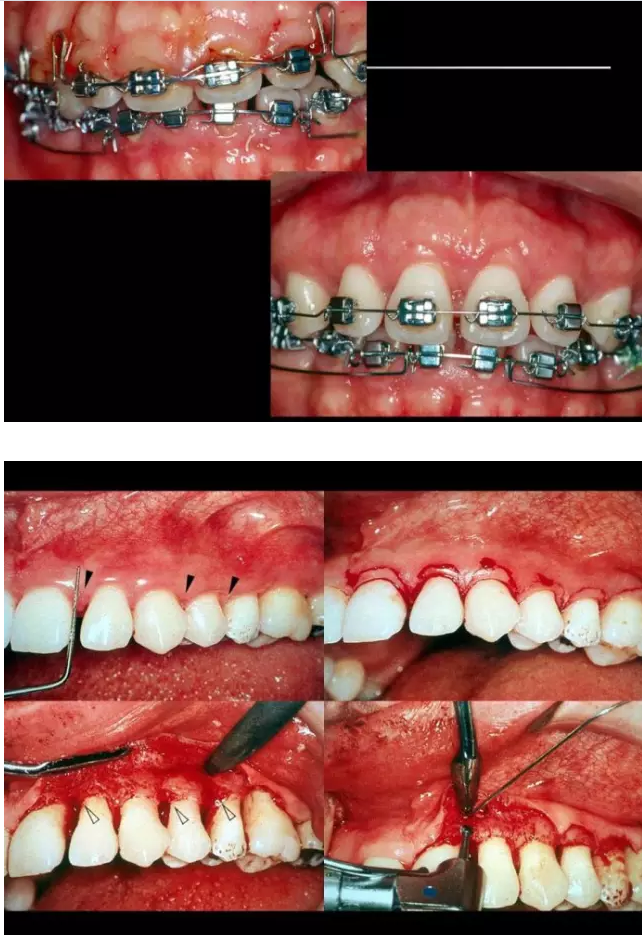

相關(guān)牙周防治